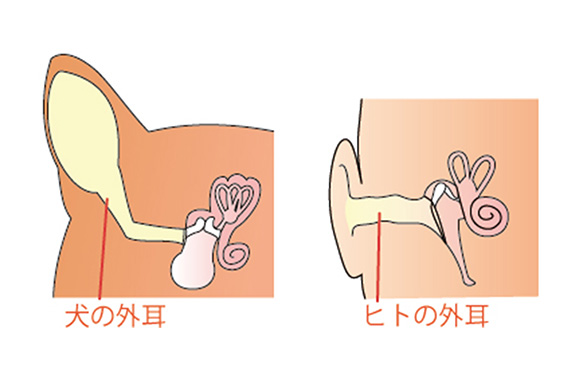

犬の耳は、愛らしい「たれ耳」や勇猛に見える「たち耳」など犬種によってカタチもさまざまですが、人間の耳と大きく違うのは実は、耳の穴が深くて長く、途中でL字型に折れ曲がっていること。そのため、これまでの一般的な検査器具では耳の奥や鼓膜の状態は確認することができませんでした。耳の奥の正確な診断ができなければ、効果的な治療も望めません。